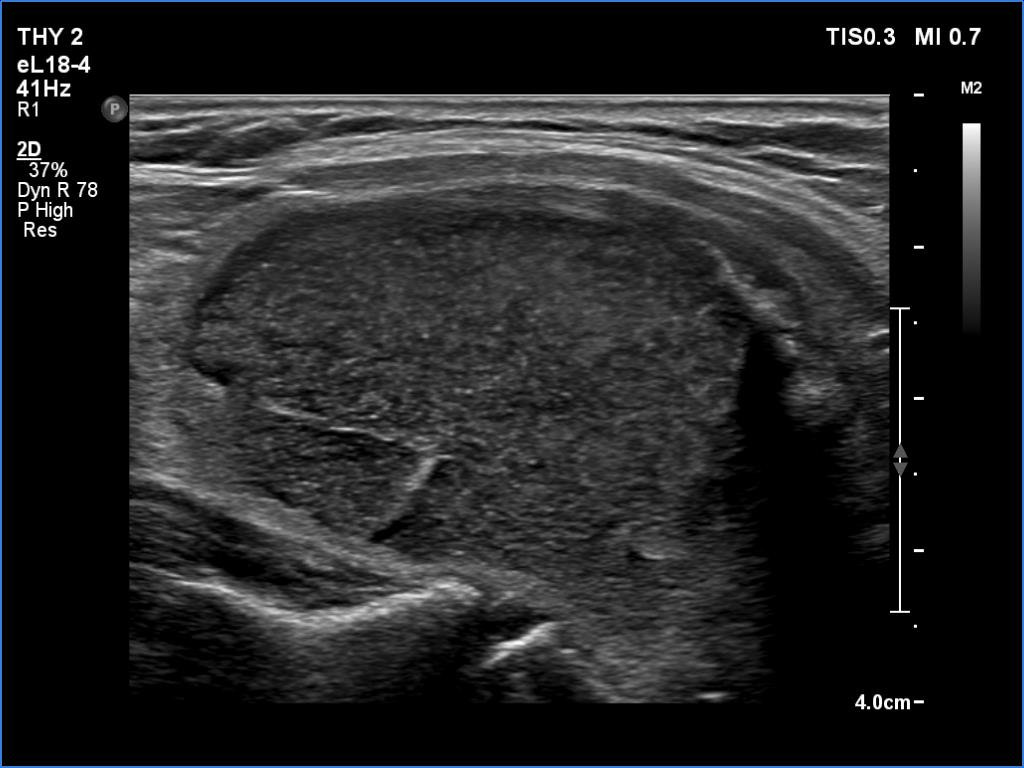

In the first part of the ultrasound examination, when the transducer was continuously moving over the thyroid gland, it was not detectable that the contents of the nodule were showing flow. When we stopped the transducer, it became clear that the seemingly solid mass was actually a dense liquid in a continuous flow. On Doppler examination, 'circulation' was visible in continuously changing places.

14 mL thick yellow fluid was aspirated. Cytology resulted in cystic fluid only, Bethesda I category.

This case illustrates two rare phenomena. On the one hand, a dense liquid may appear to be a solid tissue. On the other hand, the Doppler assay actually detects fluid flow. In the vast majority of cases, of course, this displays a circulation in the blood vessels, but in the case of cysts, when pressure is applied to the fluid with the probe, a flow is created. In the case of flow in blood vessels, circulation is always seen in the same place, while in the case of flowing cystic fluid, the flow can be detected in constantly changing places.